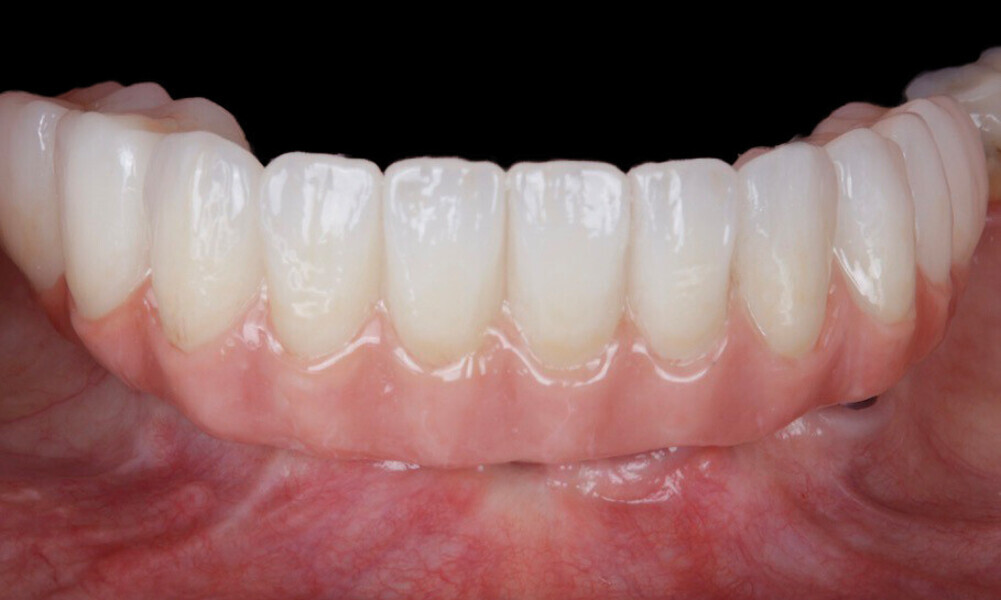

After a healing period of five months and successful osseointegration, the process for the definitive restorations was initiated. The chosen material was milled monolithic zirconia, and Variobase final abutments was used, placed on the screw-retained abutments to ensure excellent stability and retention of the definitive restorations (Figs. 69–75).

Figs. 69–75: The definitive restorations were fabricated after a five-month healing period

The soft tissue was in good condition, and the definitive restorations were placed (Figs. 76 & 77). After placing the definitive restorations, oral hygiene instructions were given to ensure proper care and prevent complications. Additionally, the occlusion was carefully checked and adjusted as needed (Figs. 78–83).

Figs. 78–82: The definitive restorations were placed, and occlusal adjustments were performed.

Fig. 83: The definitive restorations were placed, and occlusal adjustments were performed.